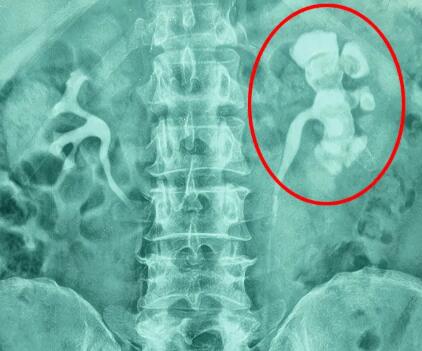

QQ截图20260124141111.jpg

这类人群即便没症状,也建议每年做一次泌尿系彩超检查。